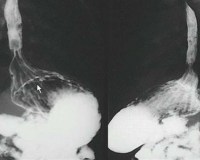

• Рентгенография. При общем рентгенологическом исследовании грудной клетки видны контуры желудочного пузыря и его верхней части в необычном месте. Для уточнения анатомических особенностей рекомендуется диагностика с контрастированием в полости рта: на фото пищевод короткий, без перегибов, бороздка расположена над диафрагмой.